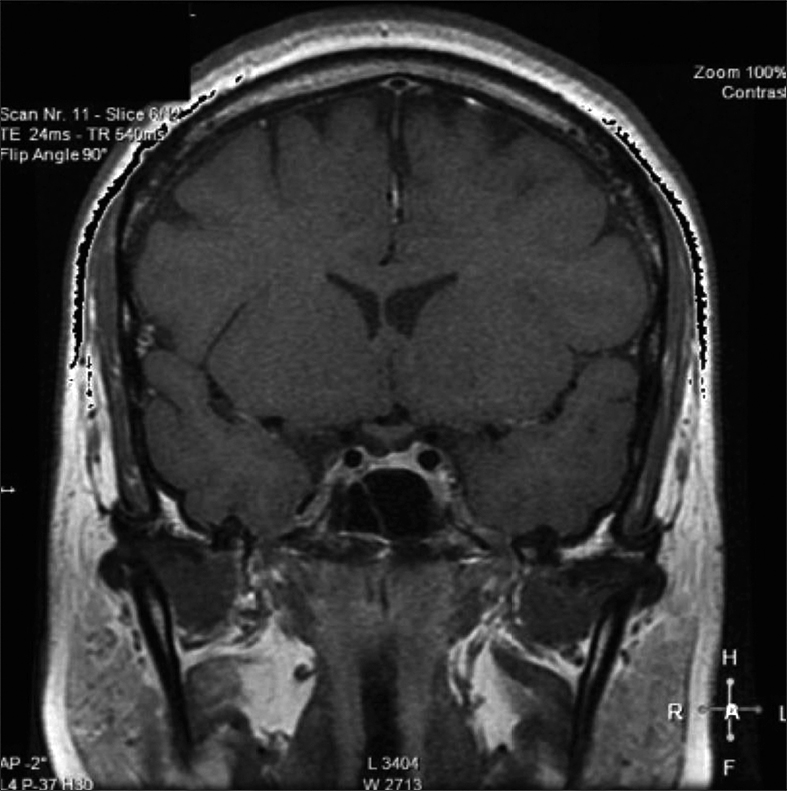

Posteriormente, consultó con especialista endocrinólogo donde se le solicitó exámenes que destacaba: glicemia 97 mg/dl, creatininemia 0,71 mg/dl, sodio 145 mEq/l, potasio 3,6 mEq/l, cloro 105 mEq/l, FSH 3,8 MUI/ml, Estradiol 12 pg/ml, prolactina 20,6 ng/ml, TSH 4,69 UI/ml, T4 libre 1,0 ng/dl, IGF-1 30,8 ng/ml (130-354), cortisol 151 ng/ml (40-230). Resonancia magnética (RM) de la región selar informó “silla turca normal, engrosamiento nodular del tercio medio distal del tallo hipofisiario y no se identifica señal de la neurohipófisis” (Figura 1). Se ajustó DDAVP a 2 puff en la mañana y 1 puff en la tarde, logrando ya normalizar la diuresis diurna y no tener nicturia. Se solicitó control RM en forma precoz para evaluar evolución de engrosamiento del tallo y segunda resonancia informó “no se identifica señal de neurohipófisis, evolución regresiva del engrosamiento del tallo hipofisiario respecto a RM previa” (Figura 2). Se establece diagnóstico de Infundibuloneurohipofisitis, Diabetes Insípida central y amenorrea secundaria por hipogonadismo hipogonadotrópico. La paciente evoluciona en forma adecuada, asintomática, con completo control de la diuresis, y dado el compromiso gonadal y la edad se inició terapia reemplazo hormonal. Siguiente RM evidenció normalización del grosor del tallo hipofisiario, sin evidenciar la neurohipófisis.

Figura 2. Evolución regresiva del engrosamiento del tallo hipofisiario.

Dentro del correcto diagnóstico de la INH está la neuroimagen, donde la RM es el método de elección. Los hallazgos comúnmente encontrados son el engrosamiento del infundíbulo y del tallo hipofisiario (se considera engrosamiento si es mayor a 4 mm) y la pérdida de señal de la neurohipófisis (hay que considerar que el 10% de la población normal no la presenta, especialmente en ancianos). Esta asociación, ausencia de señal de neurohipófisis y engrosamiento del tallo hipofisiario, son altamente sugerentes de INH. En nuestra paciente se encontraron ambos fenómenos, y considerando la regresión del engrosamiento del tallo hipofisiario lo hacía compatible con INH. La adenohipófisis en la RM es usualmente normal en tamaño e intesidad a la señal. Siendo el engrosamiento del tallo hipofisiario el hallazgo cardinal a la imagenología, inicialmente se le denominaba “Stalkitis” a esta entidad10; sin embargo, la denominación INH es la más idónea debido a que anatomopatológicamente el compromiso es del infundíbulo, tallo y neurohipófisis. Respecto al engrosamiento del tallo hipofisiario en muy importante considerar su diagnóstico diferencial9. Una adecuada historia clínica, manifestaciones clínicas, imagenología y en ocasiones biopsia darán el diagnóstico adecuado. En la Tabla 1 se enumeran las etiologías de engrosamientos del tallo hipofisiario aisladas.